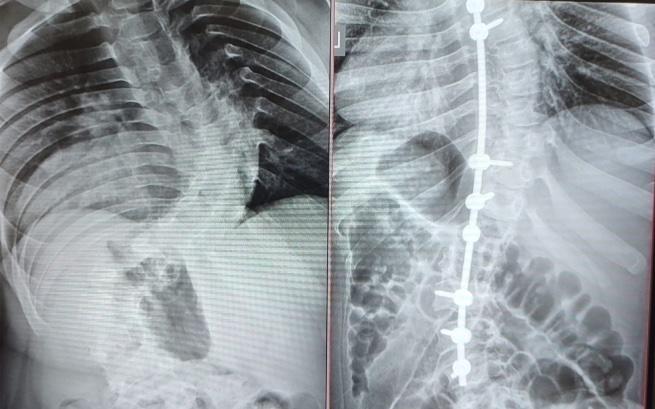

Mikołaj przeszedł operację kręgosłupa! To jednak nie koniec walki...

Mikołaj jest już po operacji kręgosłupa! W przyszłości czeka go prawdopodobnie kolejna, aby wzmocnić efekt pierwszej i zagwarantować stabilność kręgosłupa, ale już teraz cieszymy się z postępów!

W kwietniu zaplanowana jest również operacja nóg. Jest to niezbędne, aby nasz syn mógł chodzić. Dotychczas zebrane środki chcemy przeznaczyć na intensywną rehabilitację, której Mikołaj potrzebuje tak naprawdę codziennie. Niestety, koszty są ogromne i wciąż nie wystarcza nam środków...

Niestety, jednym z jego najpoważniejszych problemów jest ogromna skolioza kręgosłupa, która postępuje w zastraszającym tempie i z dnia na dzień ogranicza świat naszego małego wojownika. Żeby temu zapobiec i umożliwić Mikiemu jak najdłuższą sprawność fizyczną, potrzeba intensywnej rehabilitacji, która najpewniej będzie mu towarzyszyć do końca życia...